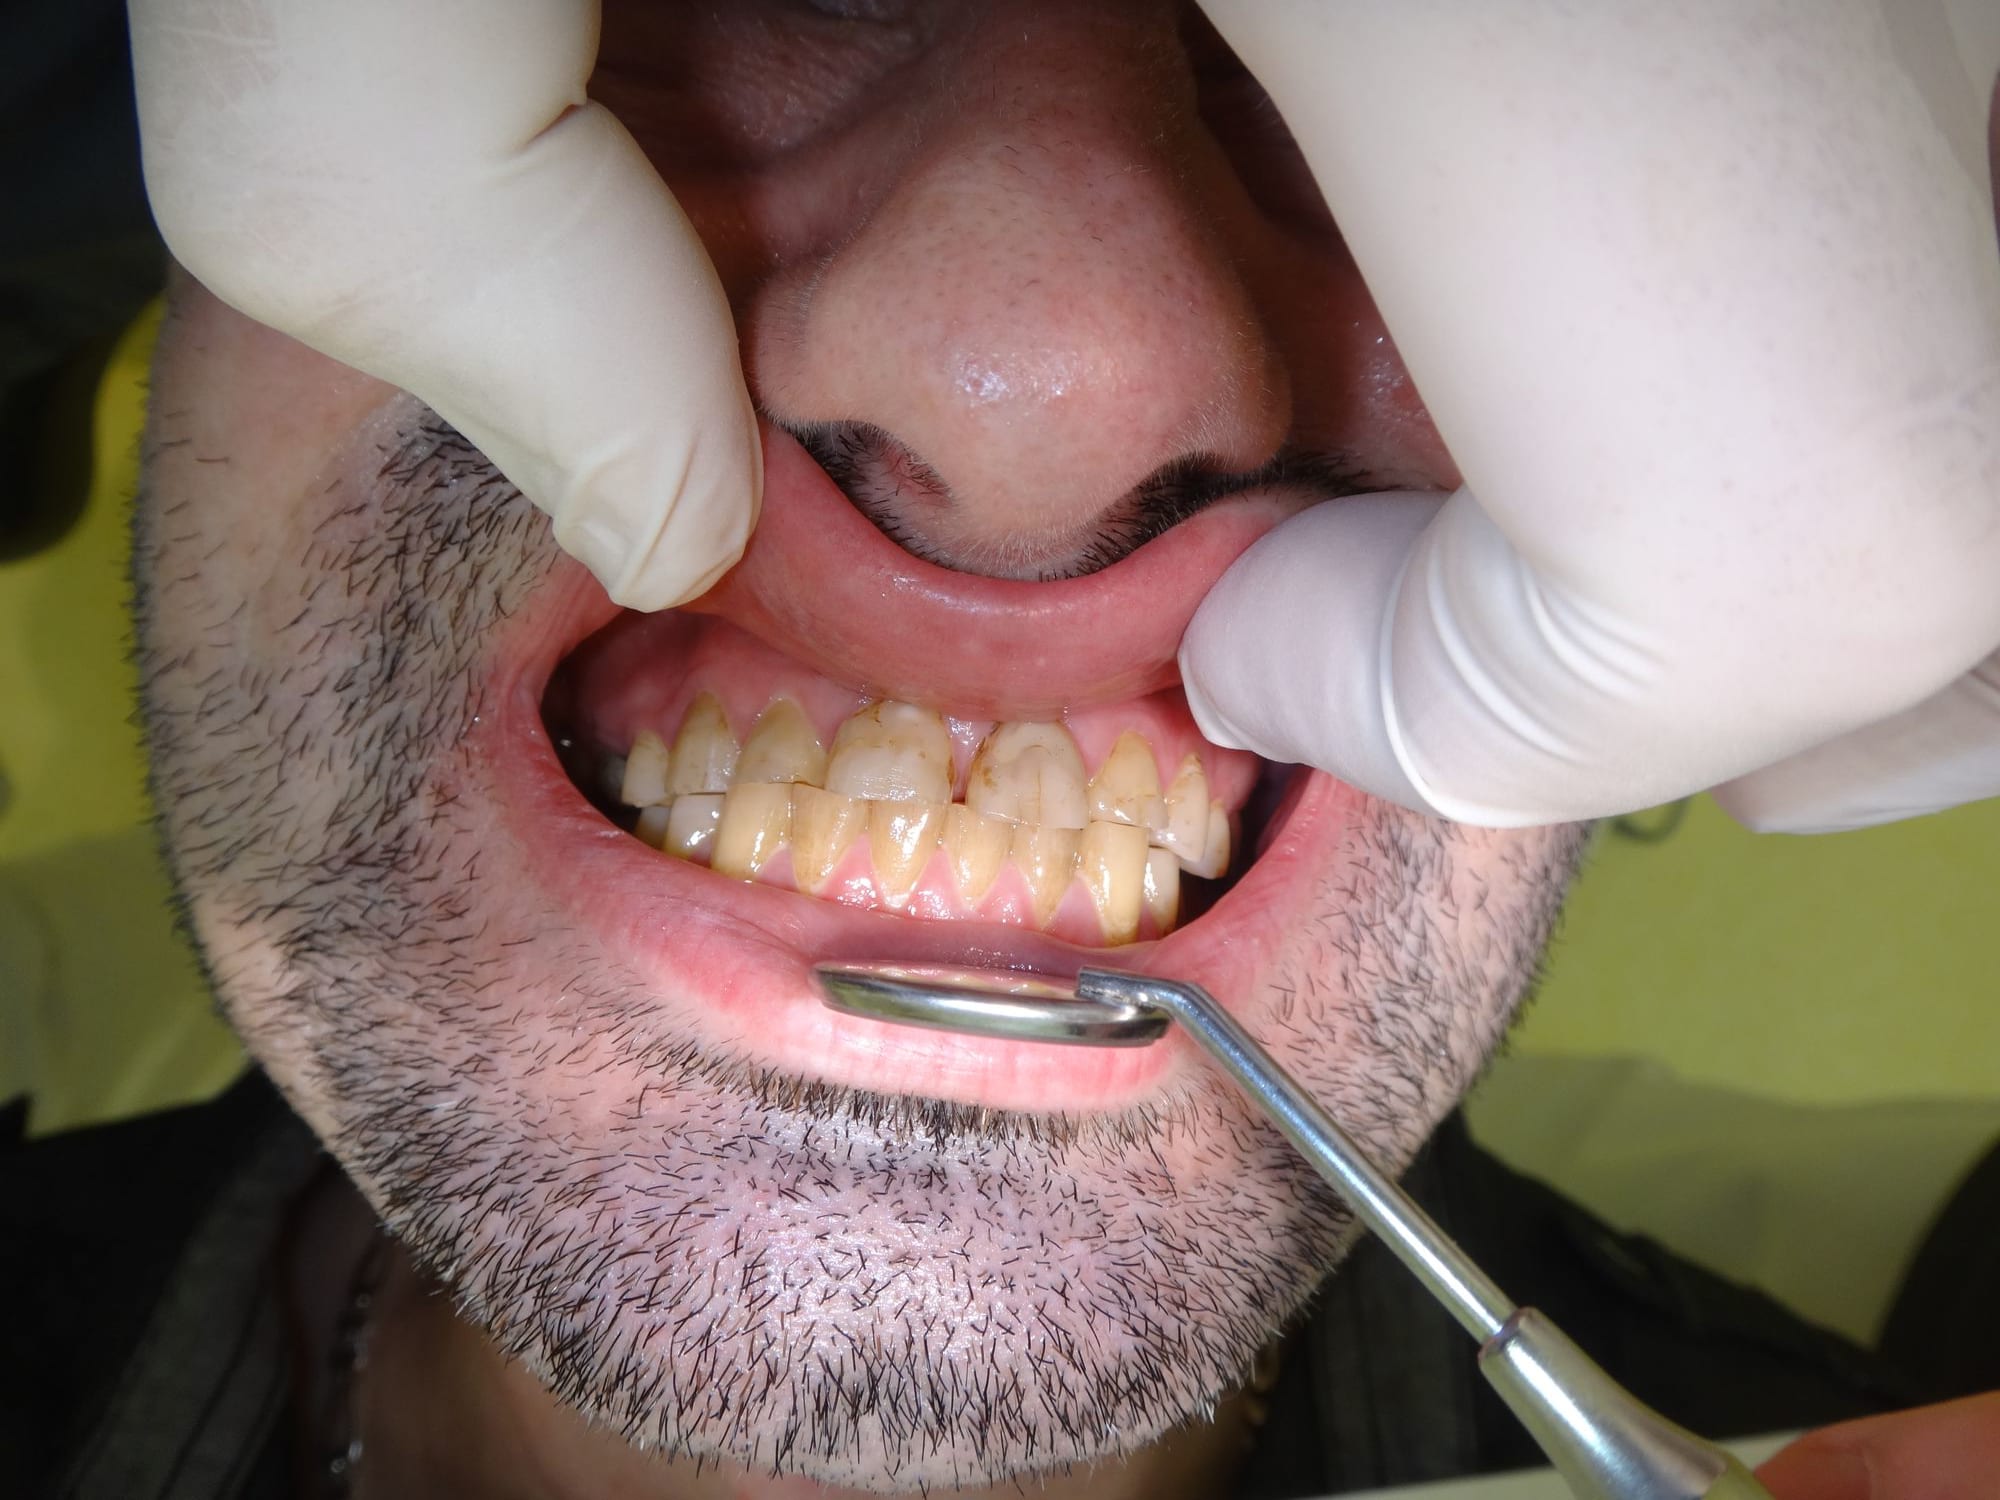

Patient 40 ans , fumeur, ex fan du coca, stressé, bruxomane forcené qui présente des érosions et abrasions chimiques généralisées.

Suite l'abrasion des dents postérieures il a une surcharge sur 11 et 21 qui sont devenues mobiles avec en plus des racines résorbées.

1/ Toutes les dts st abrasées, pas ou peu de déchaussement gingival et mobilité des incisives sup, pas de résorption radiculaire plutôt une arthrite ligamentaire. Pronostic de perte des incisives engagé à moyen terme.

2/ Os alvéolaire dense, (pas de pb de parodonte)

3/ Le Bruxisme chronique est la cause des abrasions des dts.